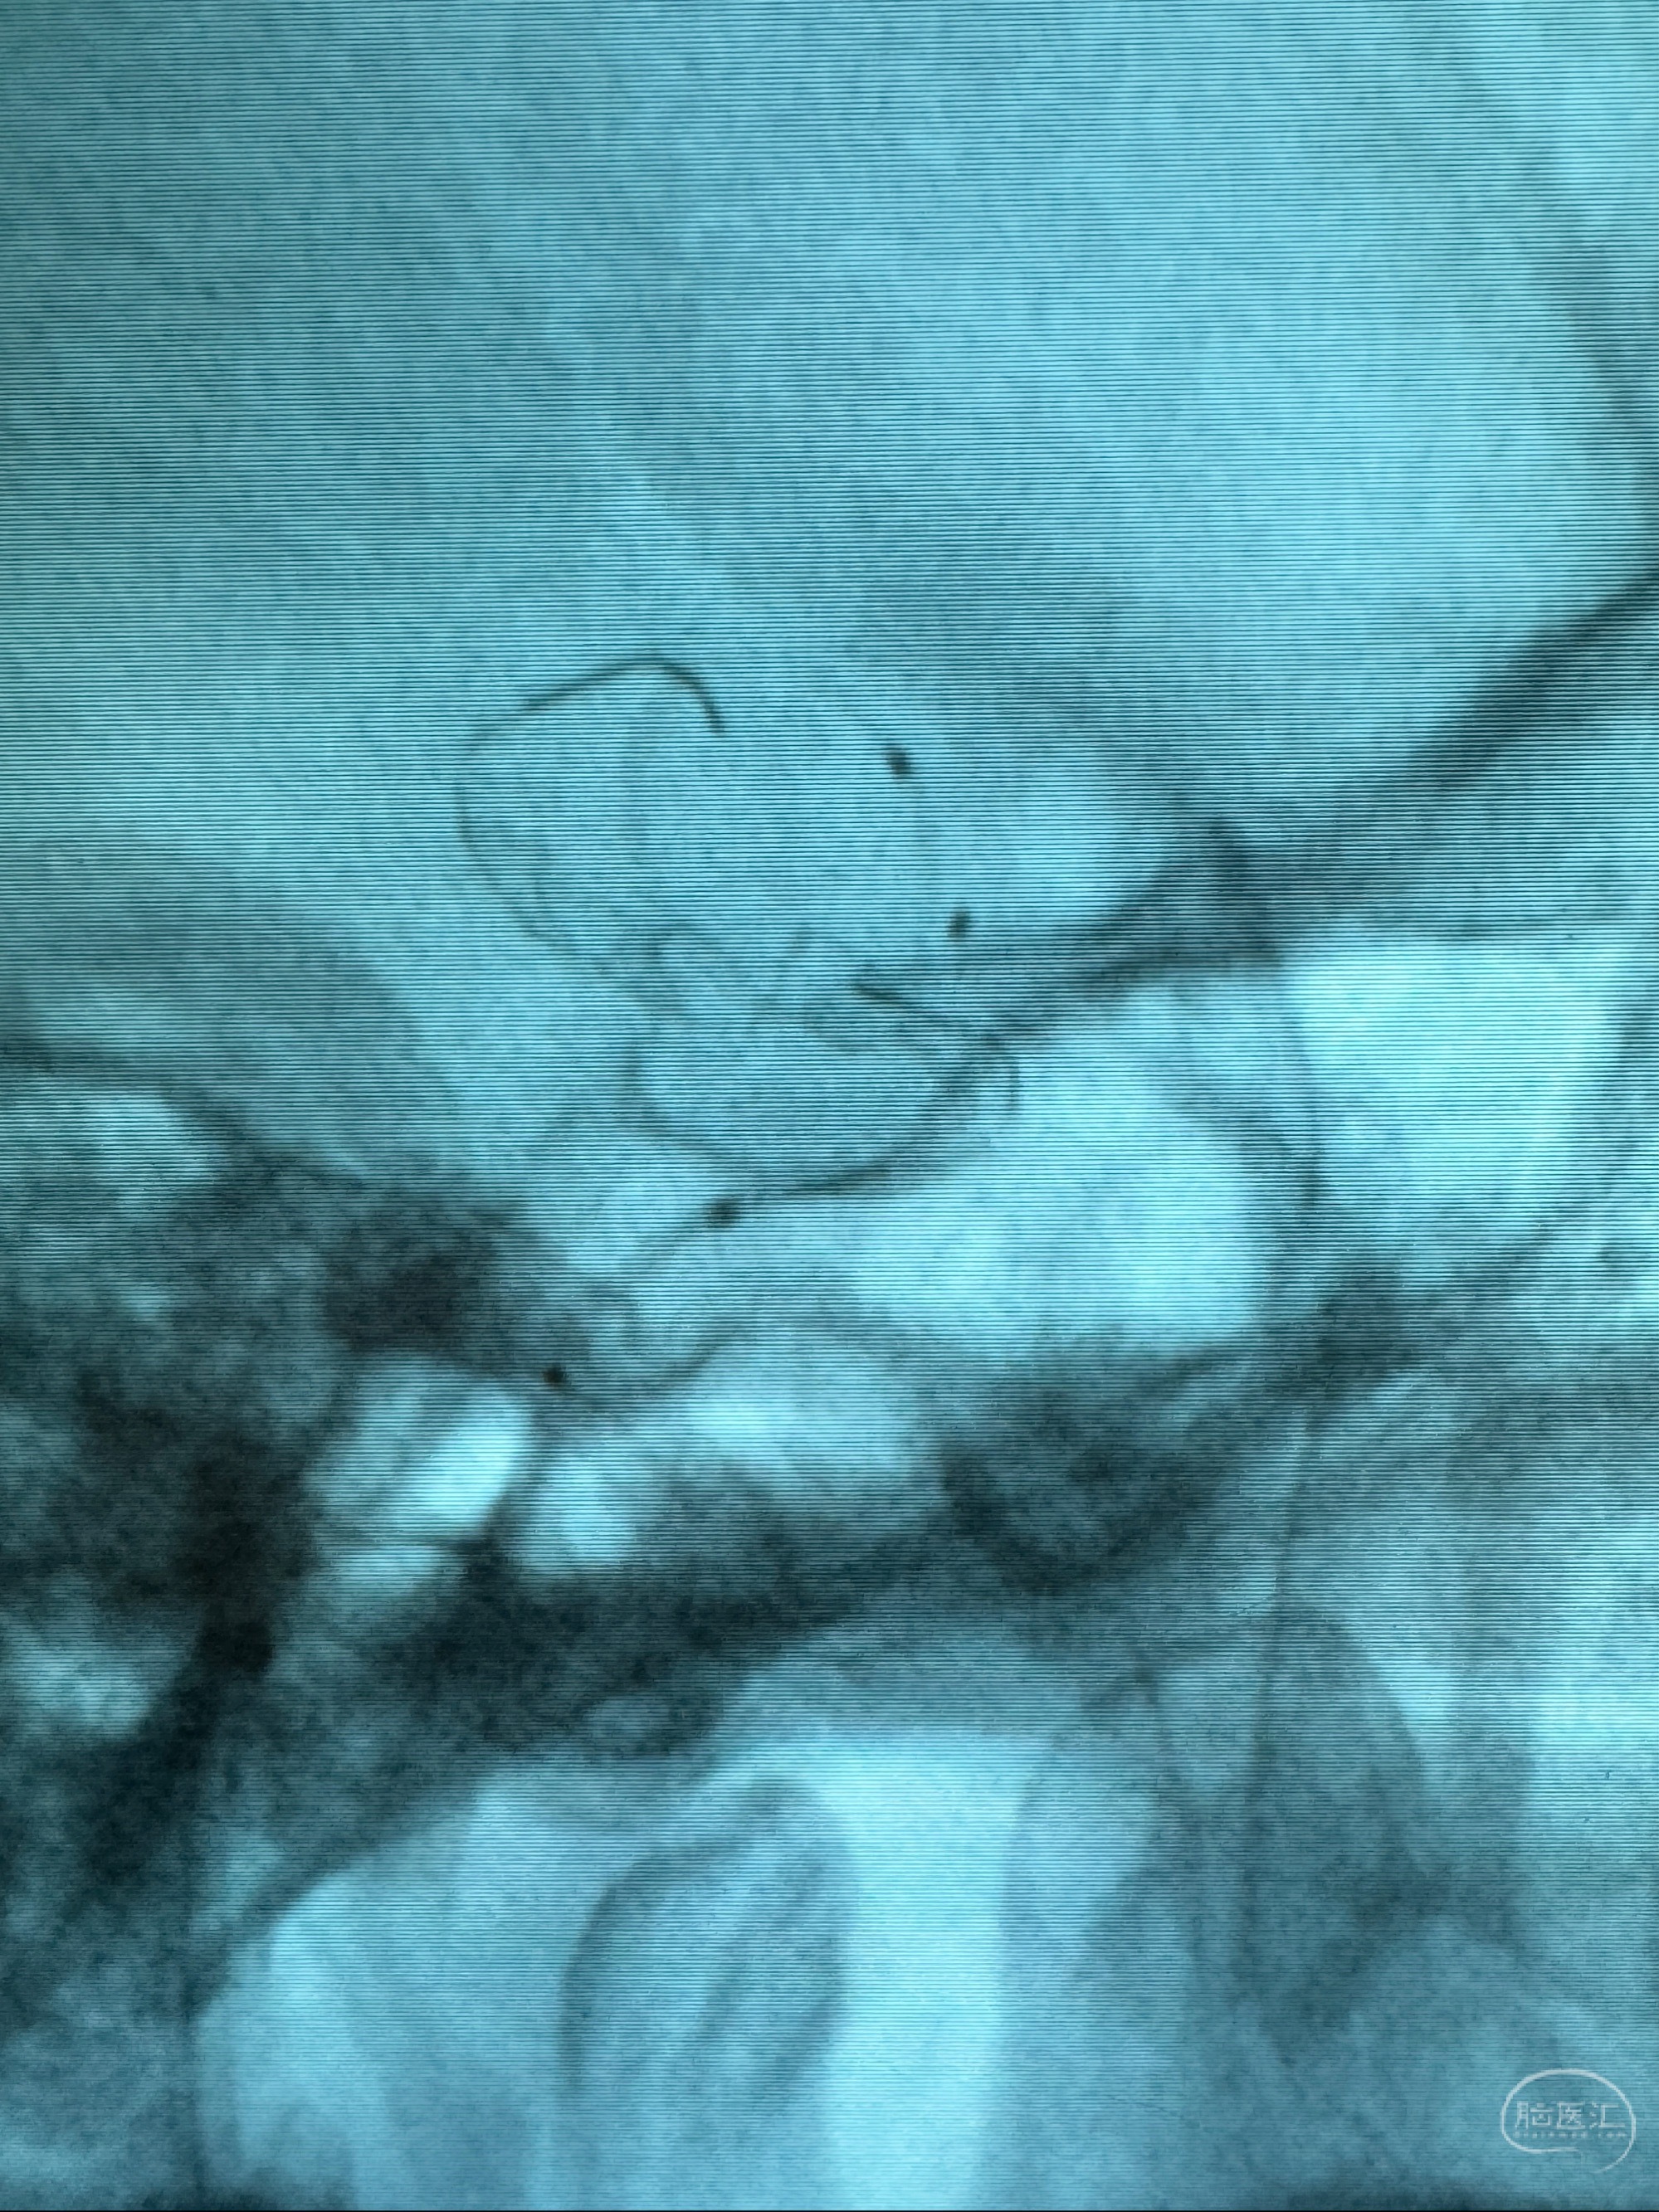

透视可见红圈部分为支架导管的头端

手推冒烟显示支架位置及展开情况,箭头为支架导管的位置

尝试回收支架失败,只能考虑释放支架了

逐帧图像展示歪着脖子释放支架,旁边吩咐助手手机摄影、拍照留像(透视机不能留影像)